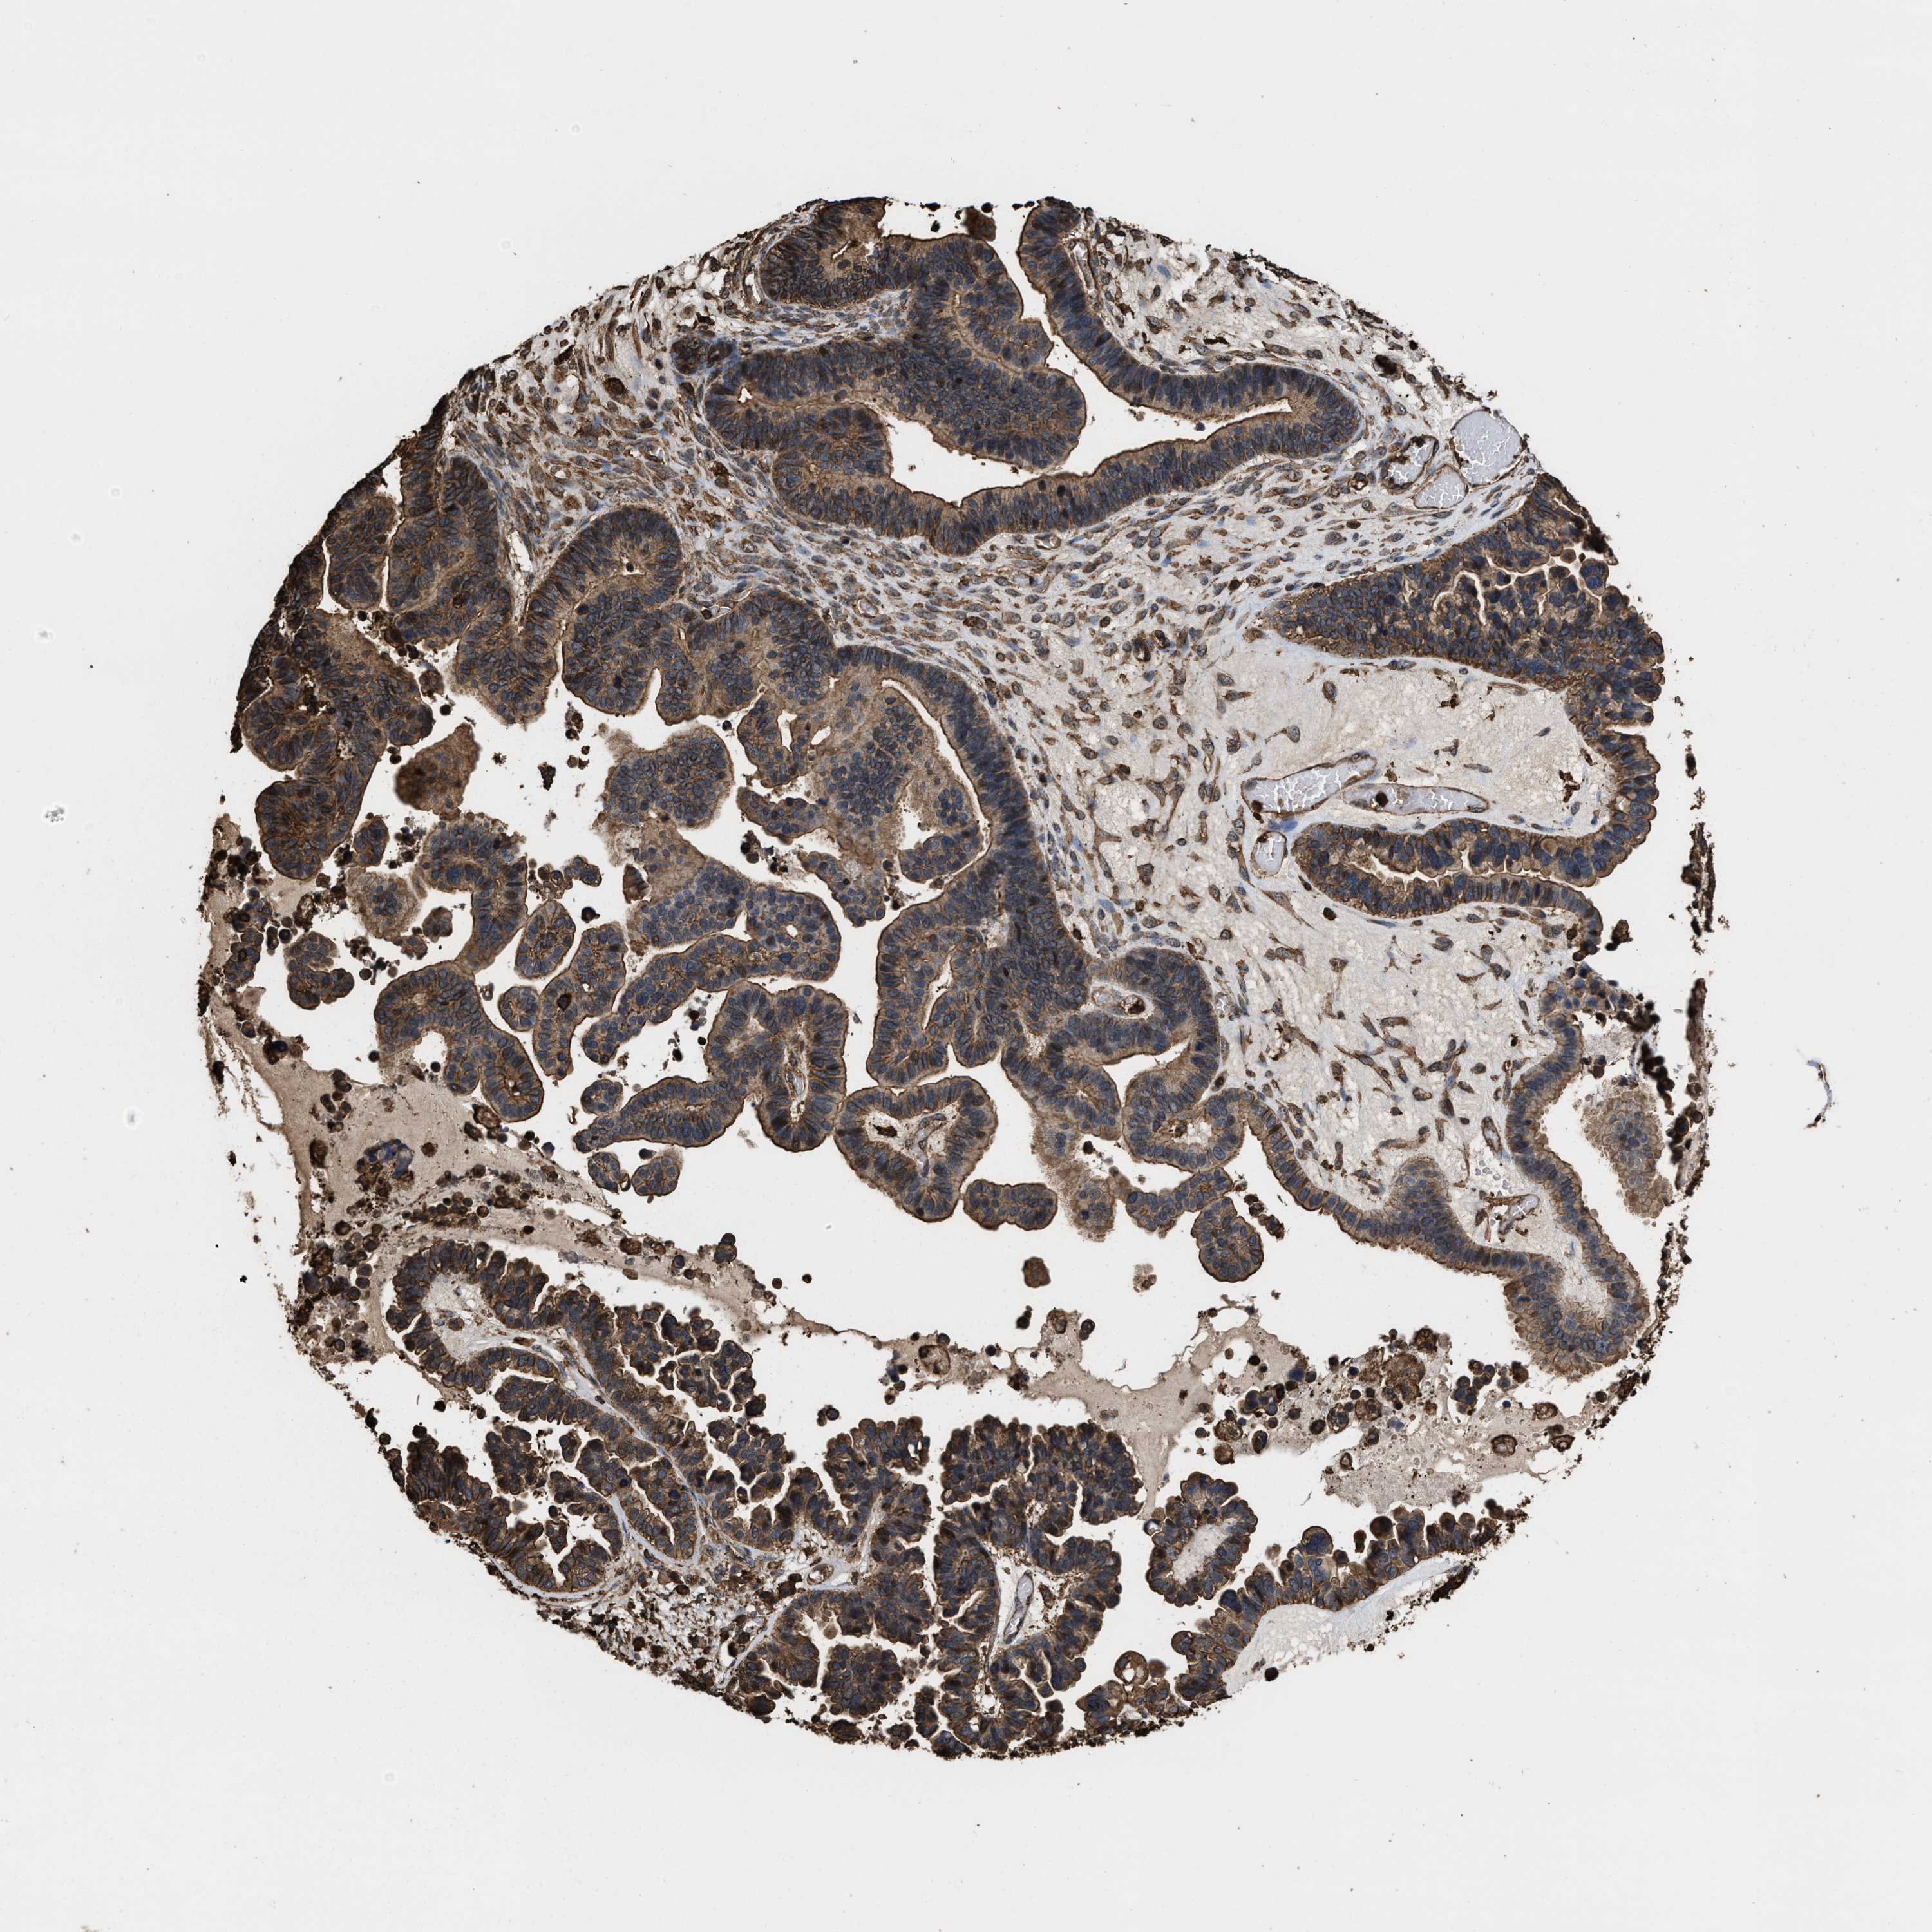

OVARIAN CANCER - Protein expressioni

A mouse-over function shows sample information and annotation data. Click on an image to view it in a full screen mode. Samples can be filtered based on level of antibody staining by selecting one or several of the following categories: high, medium, low and not detected. The assay and annotation is described here.

Note that samples used for immunohistochemistry by the Human Protein Atlas do not correspond to samples in the TCGA dataset.

Antibody stainingi

Antibody staining in the annotated cell types in the current human tissue is reported as not detected, low, medium, or high, based on conventional immunohistochemistry profiling in selected tissues. This score is based on the combination of the staining intensity and fraction of stained cells.

Each image is clickable and will lead to virtual microscopy that enables deeper exploration of all samples and also displays staining intensity scores, fraction scores and subcellular localization as well as patient and tissue information for each sample.

Antibody HPA021133

Cystadenocarcinoma, serous, NOS

Carcinoma, endometroid

Cystadenocarcinoma, mucinous, NOS

Carcinoma, NOS